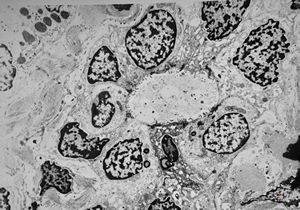

F,3m. | giant cell hepatitis - cholestasis

F,3m. | giant cell hepatitis